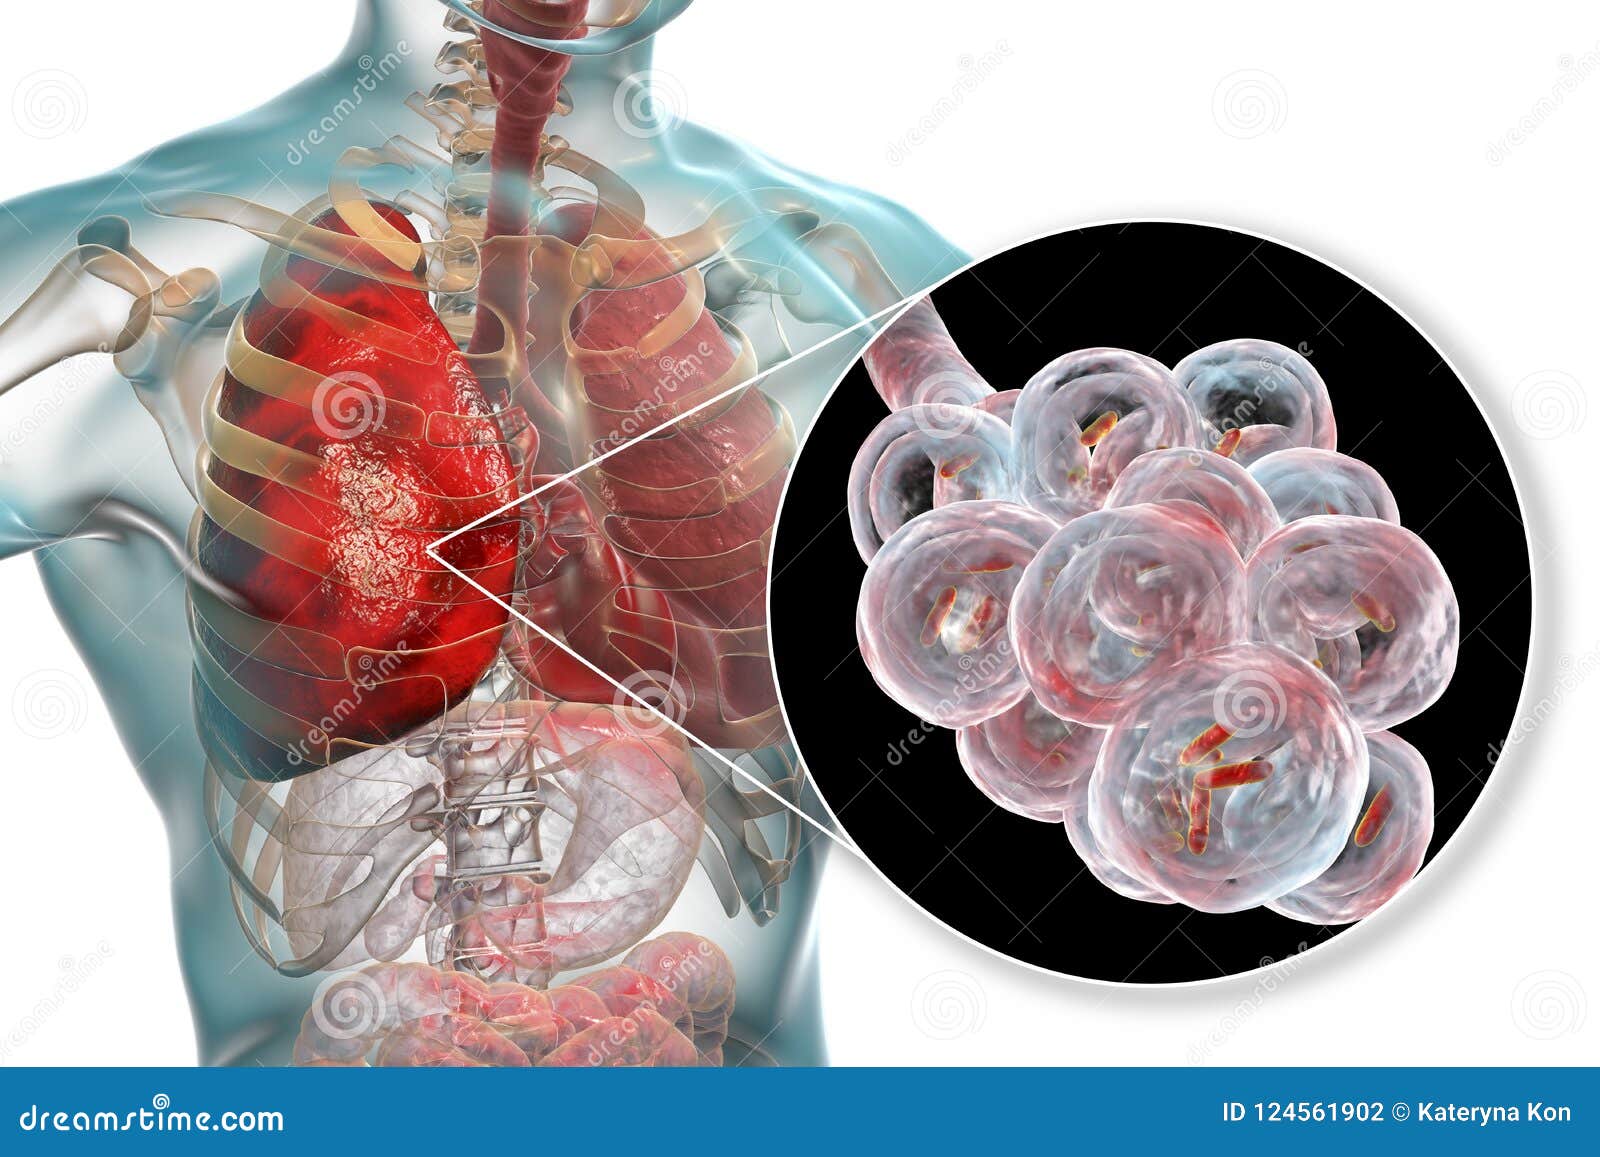

Фотографии бактерий, вызывающих бактериальные пневмонии у животных

Раздел: Другие животные